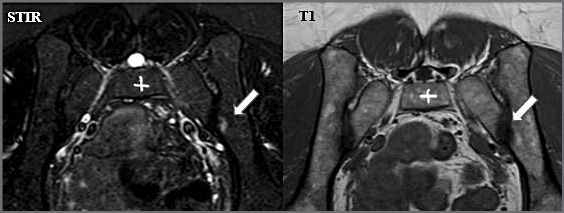

По данным магнитно-резонансной томографии (МРТ) КПС в режиме STIR в передне-среднем отделе левого КПС, со стороны подвздошной кости определяется локальный участок усиления магнитно-резонансного сигнала – активный сакроилиит слева (остеит); рис. 2.

Рис. 2. МРТ КПС в режиме STIR и T1 (аксиальный срез). Стрелкой указан отек костной ткани.

Fig. 2. SIJ MRI in STIR and T1 mode (axial slice). The arrow indicates bone tissue edema.